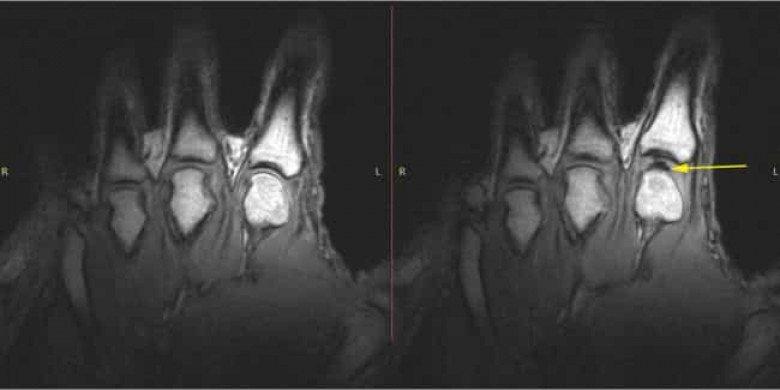

Պարզ լեզվով ասած՝ հոդը երկու ոսկորները միացնող տեղն է, որը հավաքված է հեղուկով լի կեղևի մեջ: Երբ մենք ճտտացնում ենք մեր հոդակապերը մեր ոսկորների միջև տարածքը լայնանում է: Հոդերի միջև հեղուկը բավարար չի լինում տարածքը լրացնելու համար և դրանց միջև ճնշումն ընկնում է և գազով լի փուչիկ է առաջանում: Ձայնը, որ մենք լսում ենք ճտտացնելիս, դա հենց այդ փուչիկի ճայթյունն է:

Ճառագայթաբան Ռոբերտ Դ. Բուտինը և վիրաբույժ Ռոբերտ Զաբոն ուսումնասիրել են ավելի քան 40 թեստերից ստացված արդյունքները: Թեստը հանձնաներից 30-ն ունեին իրենց հոդակապերը ճտտացնելու սովորություն, իսկ 10-ը երբեք չէին ճտտացրել:

Պարզվեց, որ հոդի շարժման ամպլիտուդան ավելի է աճում ճտտացնելուց անմիջապես հետո, ինչը նշանակում է, որ մեր հոդերն ինչ-որ կերպ տաքանում են: Սա կարող է հոդերի հիվանդություն ձեռք բերելու արդյունավետ կանխարգելում լինել: Այնուամենայնիվ, այս խնդիրը դեռ ուսումնասիրվելու կարիք ունի: